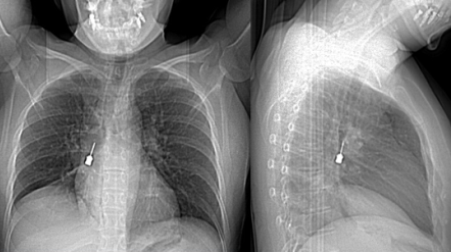

La paziente è giunta al Pronto Soccorso del G.O.M. esibendo un esame di diagnostica per immagini (Tomografia Computerizzata) eseguito a causa di una tosse persistente e di un forte dolore a livello toracico. La TC mostrava la presenza di un corpo estraneo metallico pericolosamente incastrato nel bronco lobare inferiore del polmone destro e un concomitante pneumomediastino, ossia la presenza di aria nello spazio compreso fra i due polmoni.